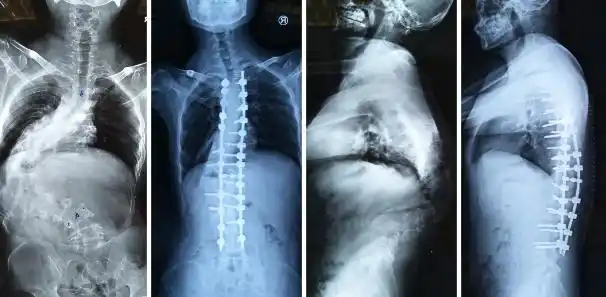

x光,脊椎

ct腰椎或l-s脊柱三维渲染图像前,后,侧位视图.

【羊城晚报】老人突发腰痛,骨质疏松椎体骨折要注意!